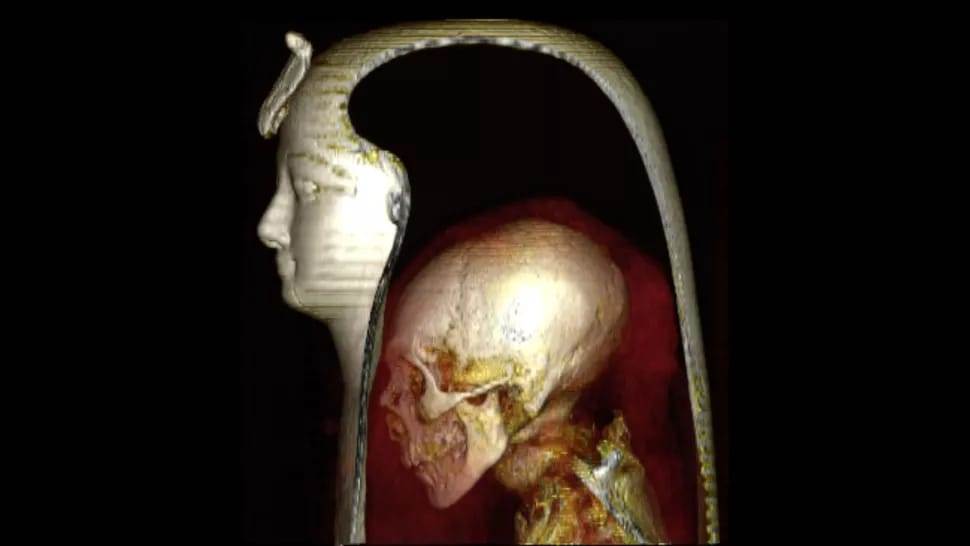

واستخدمت الدكتورة سحر سليم، والدكتور زاهي حواس تقنية أشعة متطورة من التصوير المقطعي المحوسب، وبرامج الكمبيوتر المتقدمة لفك اللفائف من على مومياء أمنحتب الأول بشكل رقمي آمن ودون الحاجة إلى لمس المومياء.

فكشفت الدراسة المصرية لأول مرة عن وجه الفرعون وعمره وحالته الصحية، بالإضافة إلى العديد من اسرار تحنيط المومياء واعادة دفنها.

وفحص العالمان المصريان مومياء الملك امنحتب الأول باستخدام جهاز التصوير المقطعي المحوسب، والموجود في حديقة المتحف المصري بالقاهرة.

واستخدم العالمان المصريان التقنيات الحديثة للأشعة المقطعية في إزالة اللفائف عن مومياء الملك أمنحتب الأول بشكل افتراضي آمن بواسطة برامج الحاسب الآلي وبدون المساس بالمومياء. فهذه التقنية تحفظ المومياء سليمة بدون لمس عكس الطريقة القديمة في فك اللفائف بشك فعلي والذي كان يعرضها للتلف.

وقال الدكتور "زاهي حواس" إن هذه الدراسة نجحت ولأول مرة منذ أكثر من ثلاثة آلاف سنة اللفائف بواسطة الكومبيوتر عن وجه الملك امنحتب الأول، والذي اتضح انه يشبه بشكل كبير والده الملك أحمس الأول والمحفوظة في متحف الأقصر. كما حددت الدراسة بشكل دقيق عمرالملك أمنحتب الأول وقت الوفاة وقدرته ب ٣٥عامًا.

وأثبتت الدراسة أن المخ لا يزال موجودا في جمجمة الملك امنحتب الأول فلم تتم إزالة المخ في عملية التحنيط على عكس معظم ملوك المملكة الحديثة مثل توت عنخ امون ورمسيس الثاني وغيرهما، حيث تمت إزالة المخ ووضع مواد تحنيط وراتنجات بداخل الجمجمة.